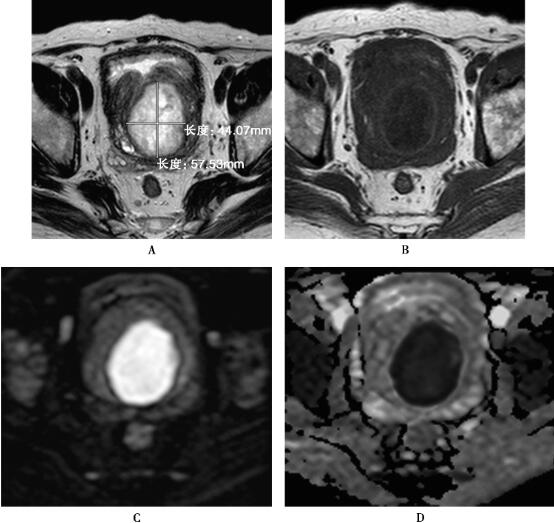

4.磁共振成像参数:所用MRI设备、线圈、脉冲序列、扫描参数及扫描方位、对比剂注射、图像后处理均与本节病例1相同。MRI表现见图1。

图1 前列腺中央腺体增生、炎症伴脓肿形成

前列腺脓肿具有特征性MRI表现,即脓腔内脓液呈T2WI高信号、T1WI低信号,因脓腔水分子扩散受限,在DWI上呈显著高信号,而ADC值显著降低;脓肿壁呈环形,T2WI低信号、T1WI等高信号;增强扫描腔内脓液无强化,脓肿壁环形强化,内壁光整。而囊肿内水分子扩散不受限,囊壁通常无强化。增强扫描和DWI提供脓肿与囊肿鉴别的关键征象,两者的诊断与鉴别并不困难。